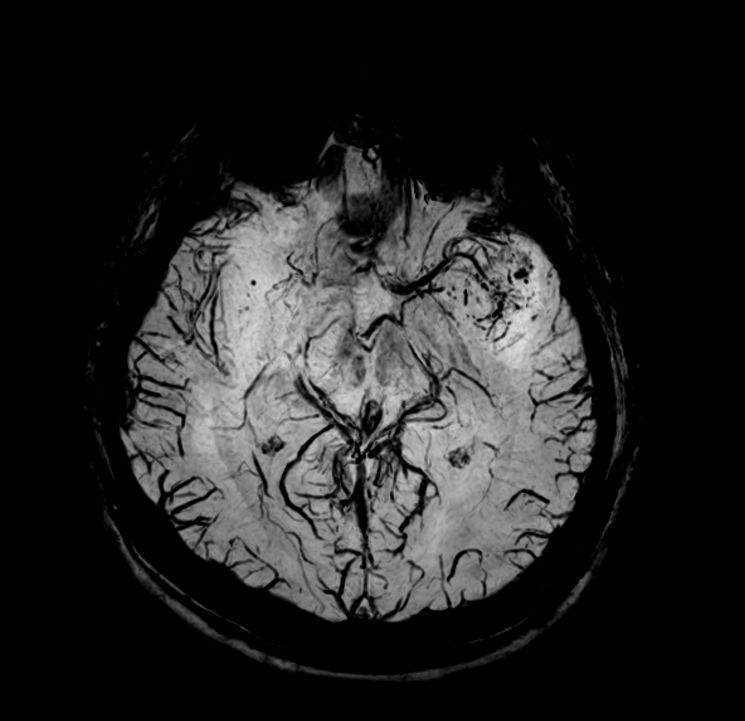

Axial SWIp (Modulus)

Axial SWIp (minIP)

Axial SWIp (Phase)